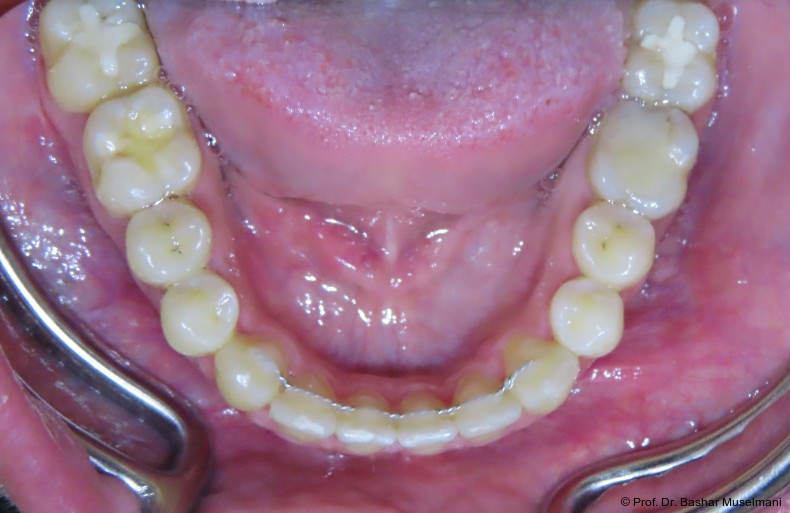

Der Patient (28 Jahre 8 Monate) stellte sich mit einer skelettalen Klasse III sowie einer Mittellinienabweichung nach links vor.

Klinische Befunde

• leicht konkaves Gesichts- und Mundprofil

• posterior positionierter Unterkiefer (VW)

• retroinkliniert stehende Unterkieferfront

Die Abbildungen 1 bis 3 zeigen die initiale klinische und radiologische Ausgangssituation.